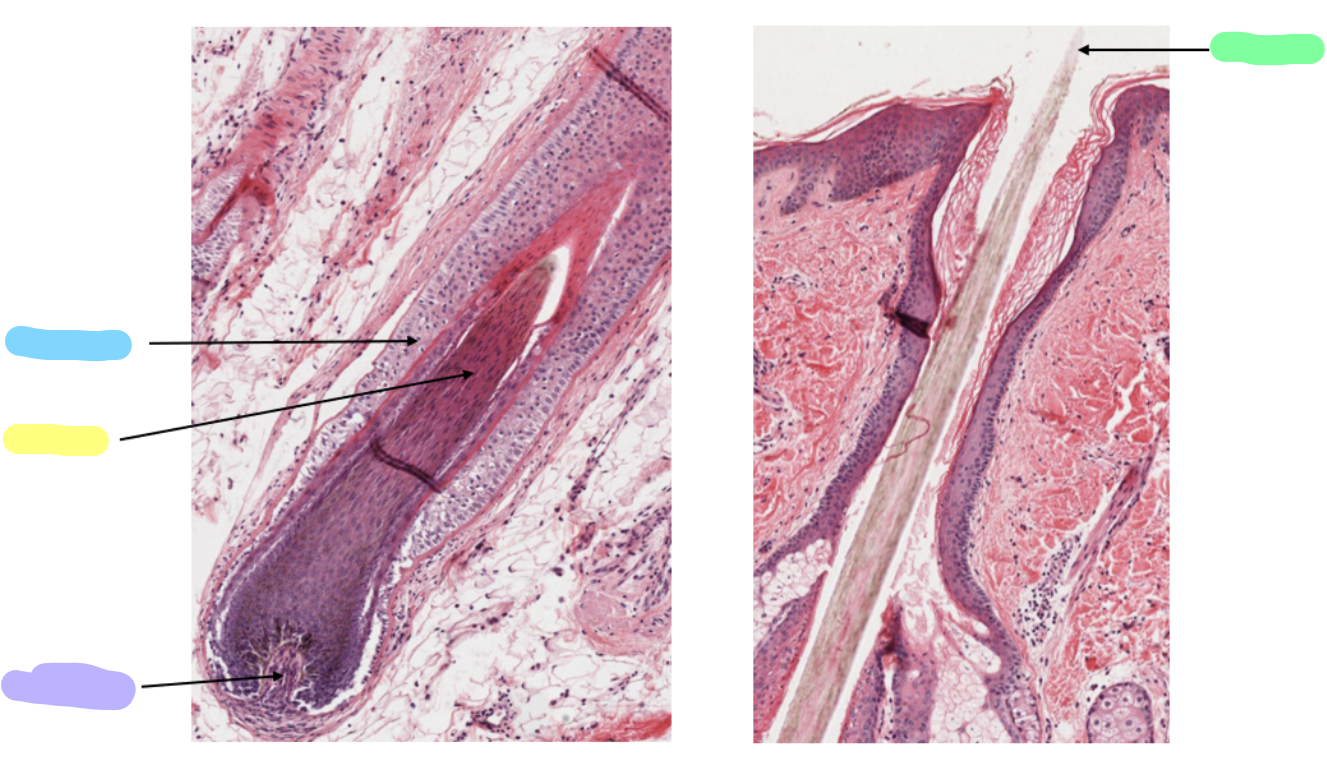

transverse section of hair

longitudinal section of hair

green

hair shaft

blue

hair follicle

yellow

hair root

purple

hair papilla

the arrows point to

arrector pili